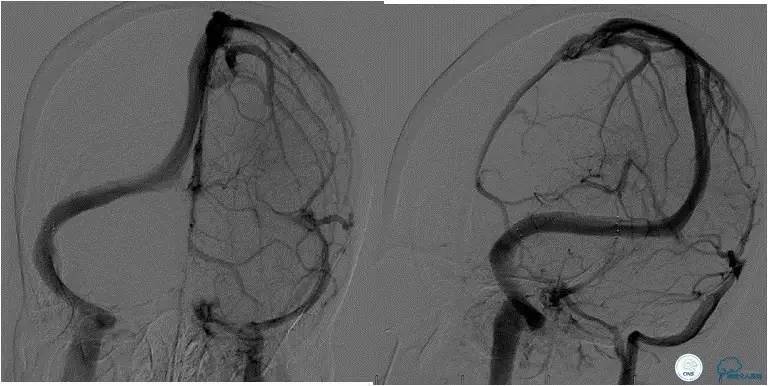

患者入院后,予以行脑动脉造影显示:右侧横窦和乙状窦交界区狭窄,左侧横窦和乙状长段重度狭窄(图3);经股静脉入路行右侧横窦和乙状窦测压显示狭窄两端压力差约为28 mmHg(图4)。遂予以阿司匹林100mg,每日一次,氯吡格雷75mg,每日一次。3d后在全麻插管下行右侧横窦-乙状窦交界处支架植入术。术中采用经右侧颈静脉入路,植入8~30mm 库克公司的ziliver支架,造影见右侧横窦-乙状窦交界处狭窄解除(图5),术中再次测压结果显示狭窄两端压力差约为1mmHg。术后自述双眼视物明显好转,但术后第3天眼底检查双视盘水肿较术前未见明显改善。

随访经过:3月后患者眼底检查双眼视盘水肿明显消退(图6),视力改善:右眼1.0,左眼0.4;8月后患者入院行脑血管造影(DSA)显示右侧横窦-乙状窦交界处支架通畅,未见再狭窄(图7)。

图3:脑动脉造影静脉窦期显示右侧横窦-乙状窦交界区狭窄,左侧横窦显影差,左侧半球血流大部分经右侧静脉窦途径引流。

图7:术后8月随访患者,脑动脉造影显示右侧横窦-乙状窦交界处未见狭窄,支架内通畅良好,未见血栓形成和内膜增生。